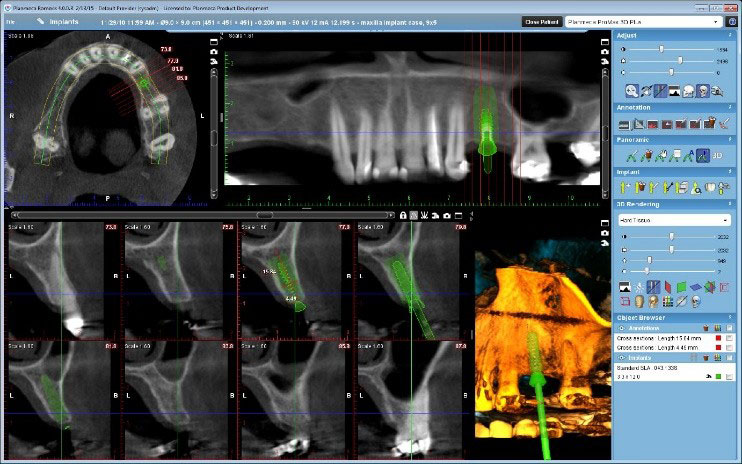

3D snimanje zuba, poznato kao konusni snimak (Cone Beam Computed Tomography – CBCT), pruža detaljan trodimenzionalni prikaz zuba, vilice i okolnih struktura. Ovaj napredni rendgenski postupak omogućava visoku preciznost u dijagnostici i planiranju tretmana, kao što su implantati, ortodontski aparati, lečenje korena i hirurške intervencije. Korišćenjem Planmeca aparata, CBCT omogućava detaljnu analizu čak i najmanjih struktura, što pomaže stomatolozima da donesu tačne i efikasne odluke za svaki specifičan slučaj.

Količina zračenja tokom 3D snimanja zavisi od veličine skenirane oblasti i veličine vokselâ (voxel size). Za aparat Planmeca ProMax 3D Mid, koji je poznat po visokoj preciznosti uz smanjeno zračenje, prosečna doza zračenja za 3D snimanje zuba je približno 10–20 mikrosiverta (µSv). Ovo je značajno niže u poređenju sa tradicionalnim CT snimanjima, koja mogu imati doze zračenja od 100–200 µSv.